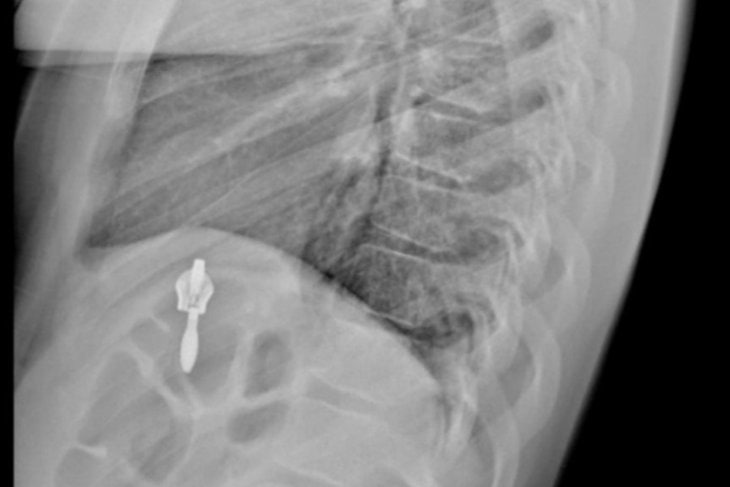

Четверо детей были госпитализированы. У всех — компрессионные переломы. Один пострадавший ребёнок получил травмы из-за гололёда, двое детей пострадали, прыгая на батутах в развлекательных центрах. Один ребёнок травмировался на соревнованиях, ещё один — на тренировке.

Фото из телеграм-канала Ивано-Матрёнинской детской больницы